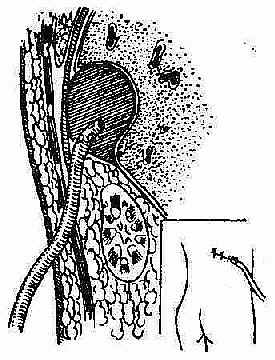

②经后腰部引流途径:此途径适用于左右膈下靠后部的脓肿,即使是右肝上间隙靠后的脓肿,也可采用此引流途径。(图2-41),方法是在局麻下沿第十二肋做切口,在骨膜下切除第十二肋(图2-42),平第一腰椎棘突平面横行切开肋骨床,然后进入腹膜后间隙,用粗针穿刺找到脓腔,再用手指插入脓腔排脓。(图2-43)。手术尽可能在直视下进行,避免误入胸腔。

图2-41 膈下脓肿经后腰部引流